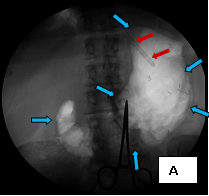

These three images illustrate a variation of how I perform percutaneous gastrostomy. Image A (supine frontal fluoroscope of the upper anterior abdomen) shows gastric insufflation after temporary gastroparesis with intravenous glucagon – distention of the stomach with air (the blue arrows outline the distended stomach) – through a nasogastric tube inserted into the stomach through the nose (the red arrows). The purpose of distending the stomach with air is to bring the anterior wall of the stomach against the anterior abdominal wall, which facilitates passing instruments of the procedure from the outside into the stomach. This is shown in Image B (a cross-table lateral fluoroscope of the upper abdomen) in which the light blue arrows outline part of the air-filled stomach; the purple arrows mark out the skin of the abdomen on which lies a pair of scissors, identifying the skin (the deep blue arrow with red outline); the black thin arrows indicate a 16 gauge needle passing from the surface of the skin into the lumen of the stomach. Image C (also a supine frontal fluoroscope of the abdomen) shows the deployed feeding tube (red arrows) within the stomach (light blue arrows).